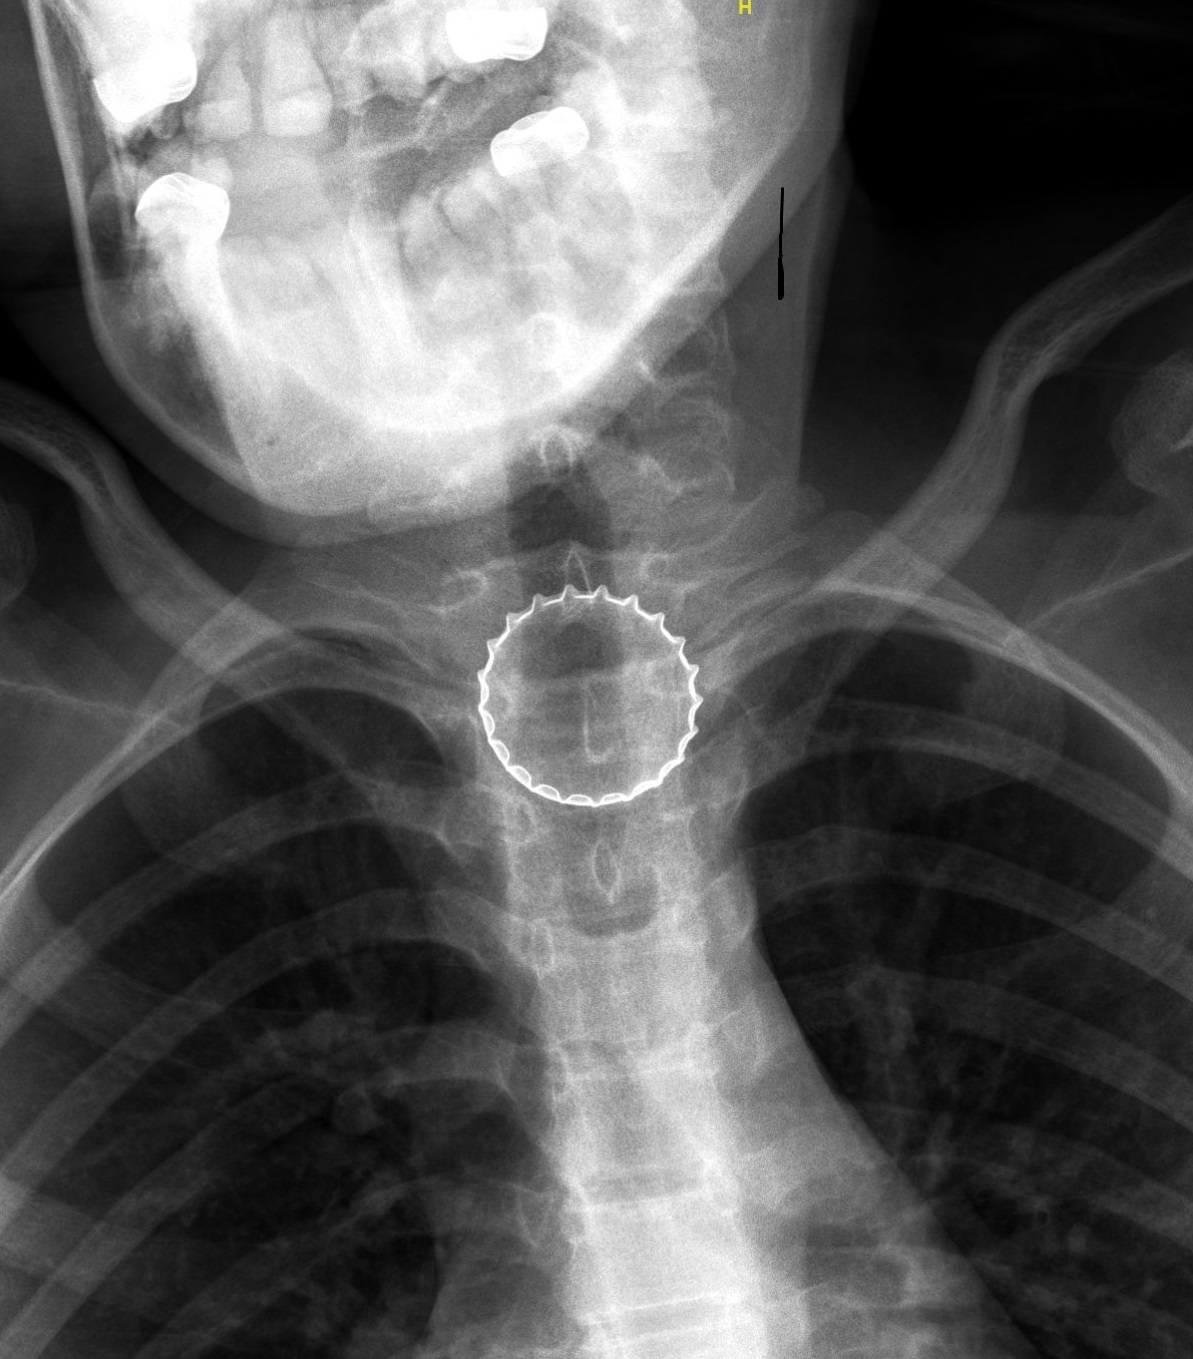

במיון ילדים עברה הנערה בירור מקיף ויסודי ע"י צוות בראשות ד"ר עלי ח'טיב, מומחה ברפואת ילדים, ובין השאר בוצע לה צילום רנטגן, בו התגלה גוף זר בוושט. הנערה הוכנסה לחדר ניתוח, שם – באמצעות ציוד אנדוסקופי ייעודי – הוצא מצינור הוושט פקק של בירה קורונה ע"י צוות ממחלקת אף אוזן גרון וניתוחי ראש-צוואר, בניהולו של ד"ר אייל סלע. הנערה אושפזה להשגחה למשך יממה ושוחררה במצב טוב.